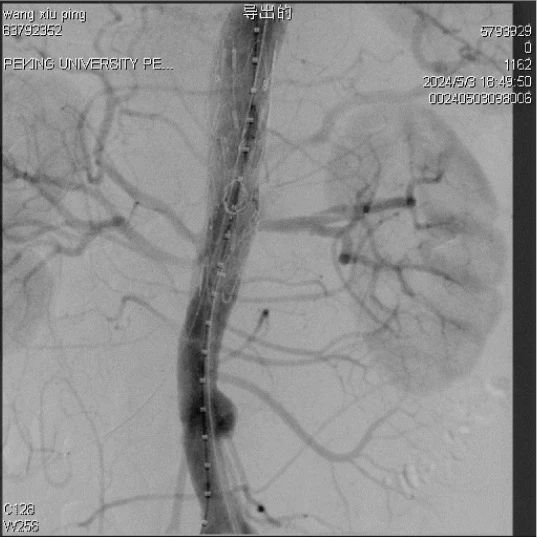

张学民教授分享了一例内脏区主动脉假性动脉瘤的治疗过程。患者女性,63岁,诊断为内脏区假性动脉瘤,病变部位累及内脏分支开口。为保护重要分支且避免内漏发生,张学民教授采用预开窗结合内分支技术重建内脏分支,器械选用彩神在线网信彩票-彩神通免费版下载-彩神8争霸vlll-彩神购彩购彩大厅-彩神软件陆立根免费版-彩神ll争霸3-彩神ll彩神8-彩神ll争霸彩票-拼搏在线彩神网网页版Ankura 24080, VB 5*50mm,VB 6*50mm, VB 8*50mm。术后造影,假性动脉瘤完全隔绝,内脏分支通畅。张学民教授指出,Ankura支架可在体内调整,确保原位开窗口与肾动脉分支对准。北京协和医院陈跃鑫教授表示,彩神在线网信彩票-彩神通免费版下载-彩神8争霸vlll-彩神购彩购彩大厅-彩神软件陆立根免费版-彩神ll争霸3-彩神ll彩神8-彩神ll争霸彩票-拼搏在线彩神网网页版Ankura支架易于回装,是内脏分支重建以及复杂病例的首选。

减小内漏风险,缝VB内分支(双斜面)

最终造影,内脏区假性动脉瘤完全隔绝